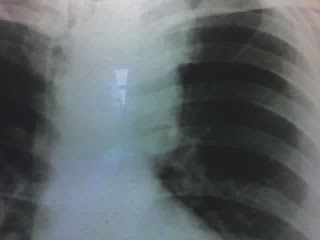

Se realizó una Rx de tórax (imagen) donde se observaba un mediastino alto ensanchado a la izquierda y una TAC que mostró una tumoración en lóbulo superior izquierdo.